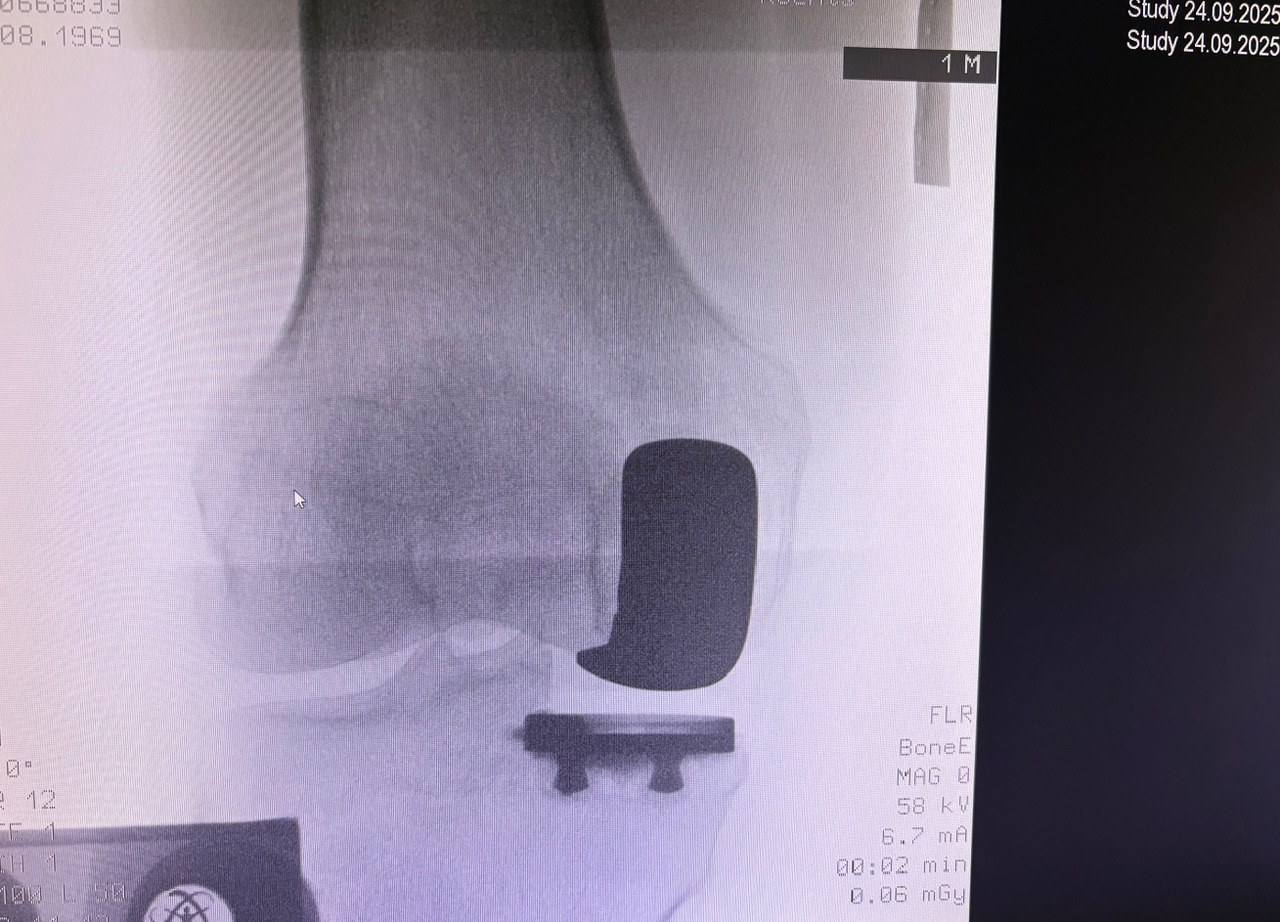

Η ημιολική αρθροπλαστική γόνατος (partial / unicompartmental knee replacement) είναι επέμβαση όπου αντικαθίσταται μόνο το φθαρμένο διαμέρισμα του γόνατος και όχι ολόκληρη η άρθρωση.

Πώς γίνεται

- Μικρότερη τομή από την ολική

- Αντικατάσταση μόνο του πάσχοντος διαμερίσματος

Η τελική επιλογή της χειρουργικής τεχνικής γίνεται μετά από αναλυτική κλινική αξιολόγηση και προσεκτικό προεγχειρητικό σχεδιασμό, με στόχο το βέλτιστο και ασφαλέστερο αποτέλεσμα για τον ασθενή. Απαραίτητη προϋπόθεση για την επίτευξη εξαιρετικών αποτελεσμάτων αποτελεί η εξειδίκευση του χειρουργού στη συγκεκριμένη τεχνική, καθώς και η εκτεταμένη εμπειρία με μεγάλο αριθμό επεμβάσεων. Ο έμπειρος ορθοπαιδικός Νικόλαος Καλύβας εφαρμόζει την Ημιολική αρθροπλαστική γόνατος (Μονοδιαμερισματική) επί σειρά ετών στη Γερμανία, έχοντας χειρουργήσει μεγάλο αριθμό ασθενών. Τα τελευταία χρόνια, από τη θέση του Αναπληρωτή Διευθυντή σε ένα από τα μεγαλύτερα κέντρα αρθροπλαστικής της Γερμανίας, είχε ενεργό ρόλο στην εκπαίδευση ειδικευομένων ορθοπαιδικών στη συγκεκριμένη τεχνική.